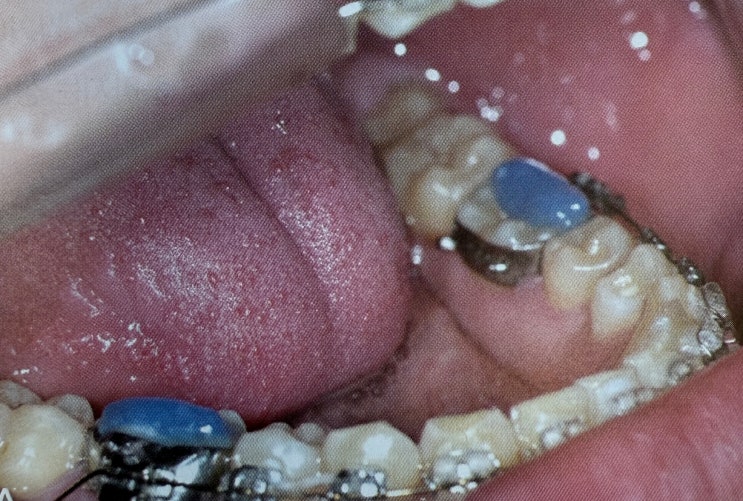

[치과임상책] 평생수제자 교정치료바이블 _ 7장 (Count down to retention)

드디어 Finishing 과정이 마무리 되었다. 꽤나 긴 여정이었지만 교정치료의 진수이기 때문에 찬찬히 읽어...

드디어 대망의 단원, 6장 피니싱이다. 공간폐쇄를 마무리 했으면 시작되는 피니싱단계는 사실상 교정치료의...